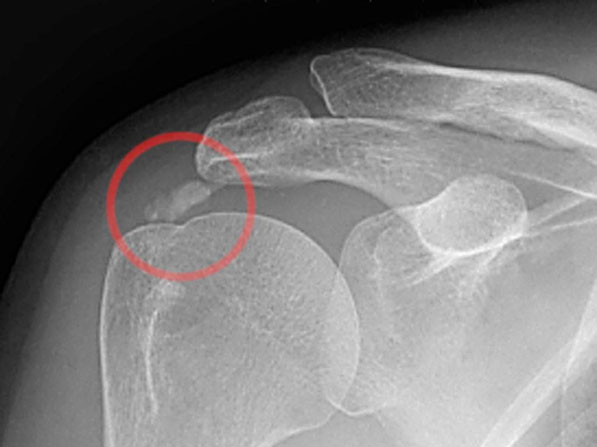

Artroszkópos kalcium depozit kiürítés

A váll meszes íngyulladásának (calcificáló tendinitis) létezik műtéti megoldása, amennyiben a konzervatív kezelés nem hoz tartós eredményt. A műtét lényege, hogy rotátorköpeny ínainak állományában felrakódott mész csomót sebészi úton kiürítjük. Az artroszkópos technikával végzett beavatkozás során rotátorköpeny külső rétegét szétválasztjuk és az alatta levő meszes ’fészeket’ alaposan kiürítjük. Előfordul, hogy az alapos mész eltávolítás érdekében az ínon nagyobb nyitást kell végezni. Ilyenkor az íngyógyulás érdekében a köpeny folytonosságát helyre kell állítani, ami a teljes felépülési időt megnyújthatja. Ezt a beavatkozást általában kiegészítjük fentiekben részletezett subacromiális decompresszióval. Rehabilitáció hozzávetőlegesen 3 hónapot is igénybe vehet.